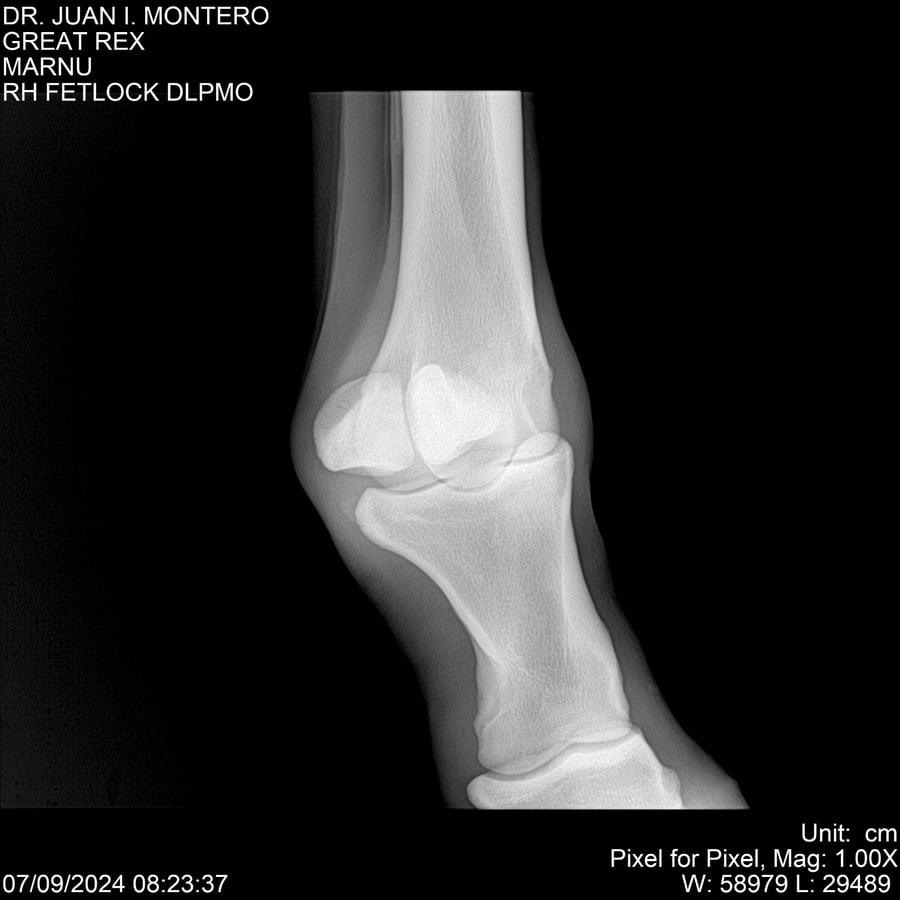

LOTE 4, GREAT REX Lote Anterior Volver al remate Lote Siguiente Ficha Contacto Montevideo - Ficha del Lote Identificador: #282518 Categoría: Yeguarizos Montevideo - 66 Visualizaciones ClicData Contacto Empresa: Abelenda N. R., Walter Hugo Nombre*: Teléfono* : E-mail* : Mensaje Enviar Registrese gratis Este contenido Exclusivo está disponible sólo para usuarios registrados Ingresar